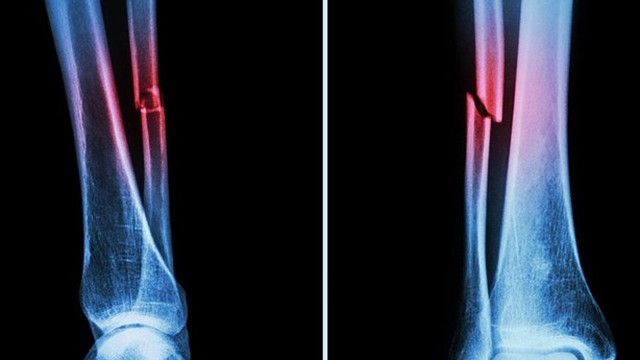

:format(webp)/gay_2_xuong_cang_chan_bao_lau_thi_lanh_bi_quyet_giup_xuong_nhanh_lien_6a7ab19d4a.jpeg)

Một trong những mối quan tâm lớn nhất của người bị chấn thương chân là gãy 2 xương cẳng chân bao lâu thì lành và có những bí quyết vàng nào có thể giúp phục hồi nhanh chóng không. Đừng lo, Nhà thuốc Long Châu sẽ bật mí cho bạn các thông tin hữu ích thông qua bài viết dưới đây nhé.